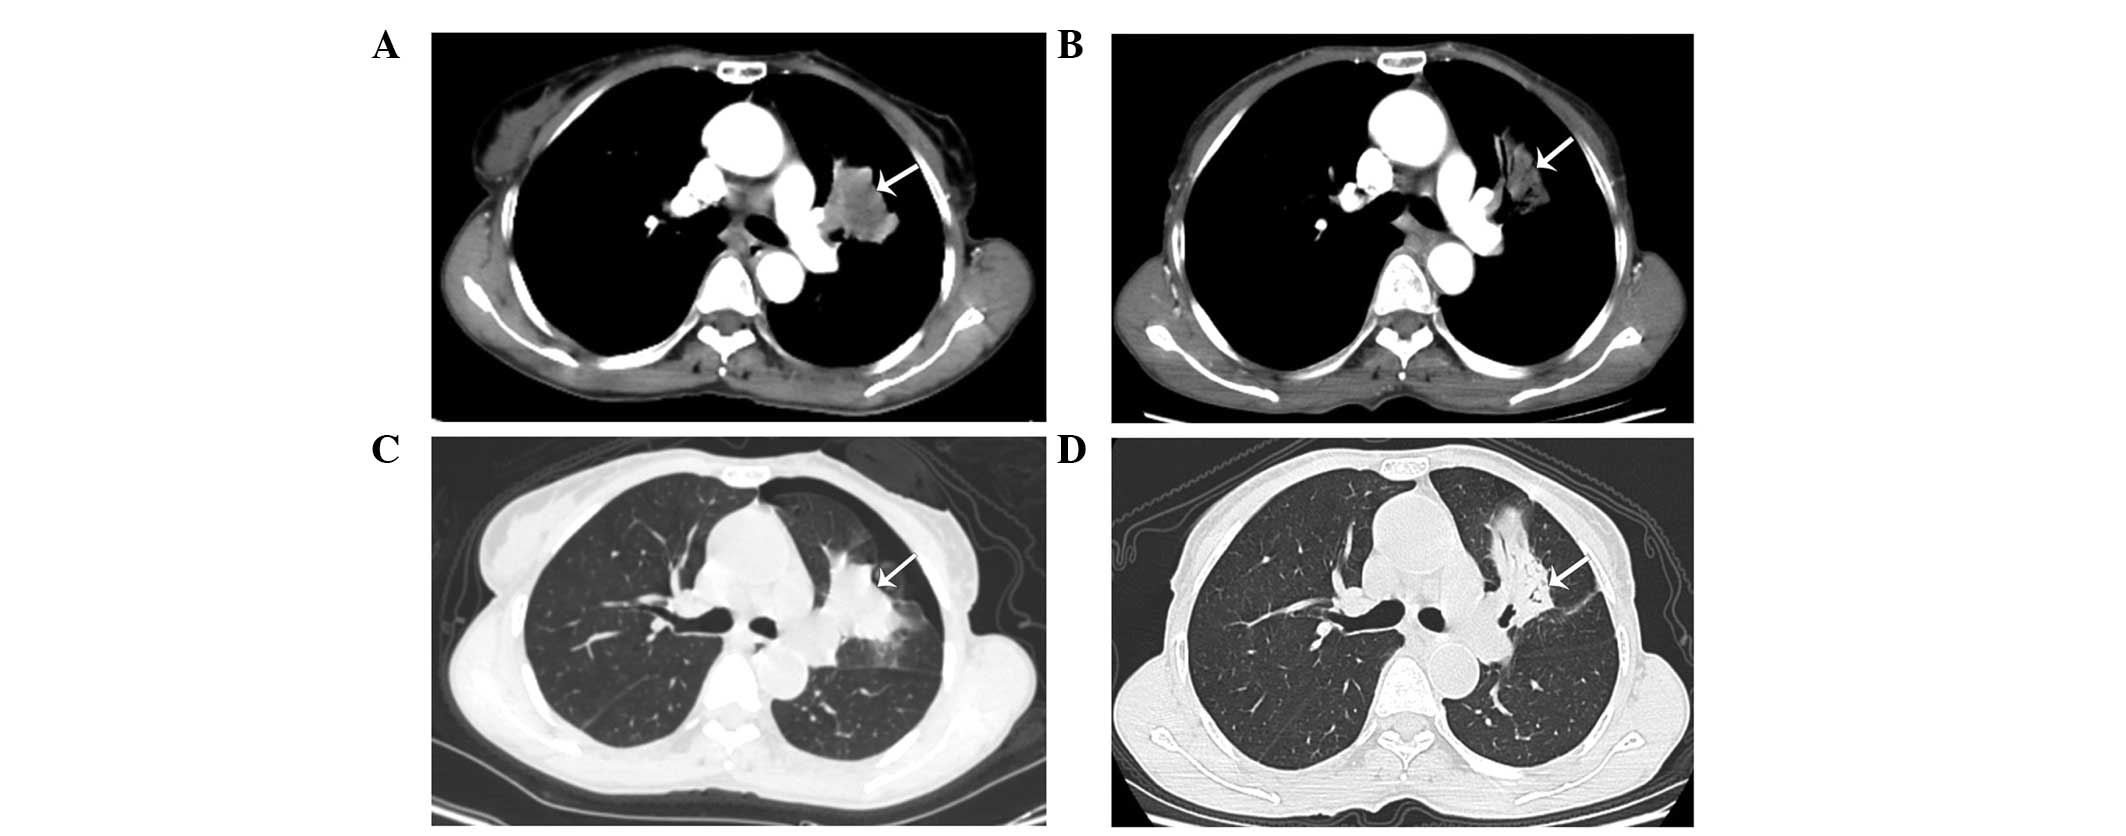

On March 10, 2014, a 62-year-old, non-smoking woman with an Eastern Cooperative Oncology Group Performance Status score of 2 (13) presented to the Department of Oncology, Comprehensive Cancer Center of Drum-Tower Hospital (Nanjing, China) with a cough that had been ongoing for 2 months. Computed tomography (CT; Discovery CT750 HD; GE Healthcare Life Sciences, Shanghai, China) revealed a primary mass in the left upper lobe of the lung (Fig. 1A and B), with multiple small pulmonary nodules (maximum diameter, 4 mm) observed bilaterally. A CT-guided fine needle aspiration biopsy of the primary lesion was performed on the left lung, which revealed the presence of a middle-differentiated adenocarcinoma. EGFR mutation analysis was performed on the biopsied tissue within exons 18 and 21. EGFR mutations were detected by amplification refractory mutation system in multiple quantitative polymerase chain reaction analysis with the Human EGFR Mutation Detection kit (YuanQi Bio-Pharmaceutical Co., Ltd., Shanghai, China), as previously described (14), which demonstrated a co-mutant of Del-19 (del 2239_2248+insC) and L858R. In addition, anaplastic lymphoma kinase rearrangement analysis was performed using fluorescence in situ hybridization, with negative results. The patient was orally administered erlotinib, at a dose of 150 mg/day. Two months later, no considerable relief of the cough was noted; however, a CT scan revealed that the primary lung mass had shrunk (Fig. 1C and D), but the bilateral multiple pulmonary nodules remained. In addition, prior to erlotinib treatment there was no hepatic metastases (Fig. 2A–C); however, following treatment multiple hepatic metastases were observed (Fig. 2D–F). Based on the Response Evaluation Criteria in Solid Tumors (RECIST) (15), the treatment response of the patient was assessed as progressive disease (PD). The patient refused to undergo a biopsy of the liver. Treatment with erlotinib was stopped when PD was detected, and 2 cycles (3 weeks/cycle) of chemotherapy with pemetrexed (500 mg/m2) plus cisplatin (75 mg/m2) were administered to the patient intravenously. However, the hepatic metastases continued to progress under the assessment of CT scans, which were performed monthly. The patient succumbed 2 months subsequent to the detection of PD, with the best supportive care possible. The patient's overall survival was ~5.3 months.

Figure 1.

Chest computed tomography scans. Presence of a left upper lobe primary mass with multiple small pulmonary nodules in both lungs was observed prior to erlotinib treatment; a left upper lobe primary mass was identified on the (A) mediastinal window and (B) pulmonary window, respectively (arrows). Following 8 weeks of erlotinib treatment the mass had shrunk on the (C) mediastinal and (D) pulmonary windows, respectively (arrows).